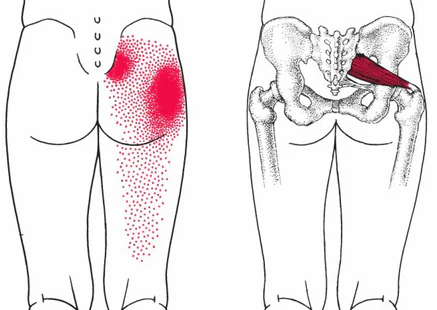

이상근증후군(좌골신경포착증후군, Piriformis Syndrome)은 엉덩이 근육 중 하나인 이상근(piriformis muscle)이 그 아래를 지나가는 좌골신경(sciatic nerve)을 압박하거나 자극하면서 발생하는 질환입니다. 이로 인해 허리디스크와 유사하게 엉덩이, 허벅지 뒤쪽, 종아리, 또는 발까지 저림, 당김, 통증, 무감각, 이상감각 등이 나타날 수 있습니다.

이상근은 고관절을 바깥으로 돌리는 기능을 하는 근육으로, 신경이 지나가는 자리와 가깝기 때문에 여러 원인에 의해 두꺼워지거나 긴장할 때 좌골신경을 압박할 수 있습니다.

엉덩이 중심의 통증이 특징적이며, 다리 뒤쪽으로 통증이 뻗는 방사통이 종종 동반됩니다.

심한 경우 허리, 사타구니, 항문 주변, 허벅지, 다리, 발 등에서도 통증이나 저림이 나타납니다.